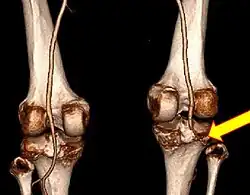

Plain X-rays, CT scan, ultrasonography, or MRI may help with the diagnosis.[2][11] Findings on X-ray that may be useful among those who have already reduced include a variable joint space, subluxation of the joint, or a Segond fracture.[5]

They may be divided into five types: anterior, posterior, lateral, medial, and rotatory.[4] This classification is based on the movement of the tibia with respect to the femur.[11] Anterior dislocations, followed by posterior, are the most common.[2] They may also be classified on the basis of which ligaments are injured.[2]